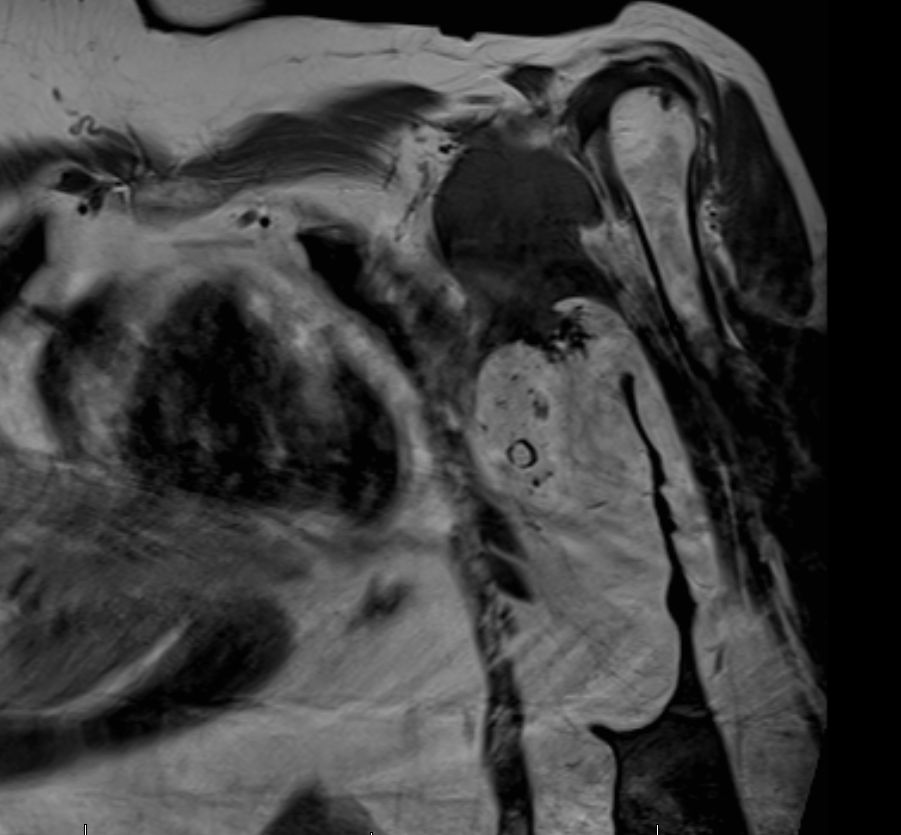

| Diagnostik | 56-jährige Frau mit einer derben, wenig verschieblichen Tumorbildung untergalb der linken Clavikula. ![]() |